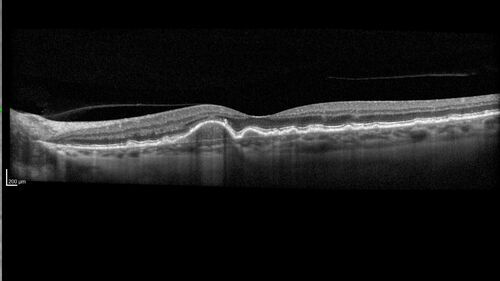

Dry AMD - Pigment - AREDS risk score of 4

65 year old woman with 20/32 vision. A little blurred. Pigment and large drusen in each eye. AREDS risk score of four.